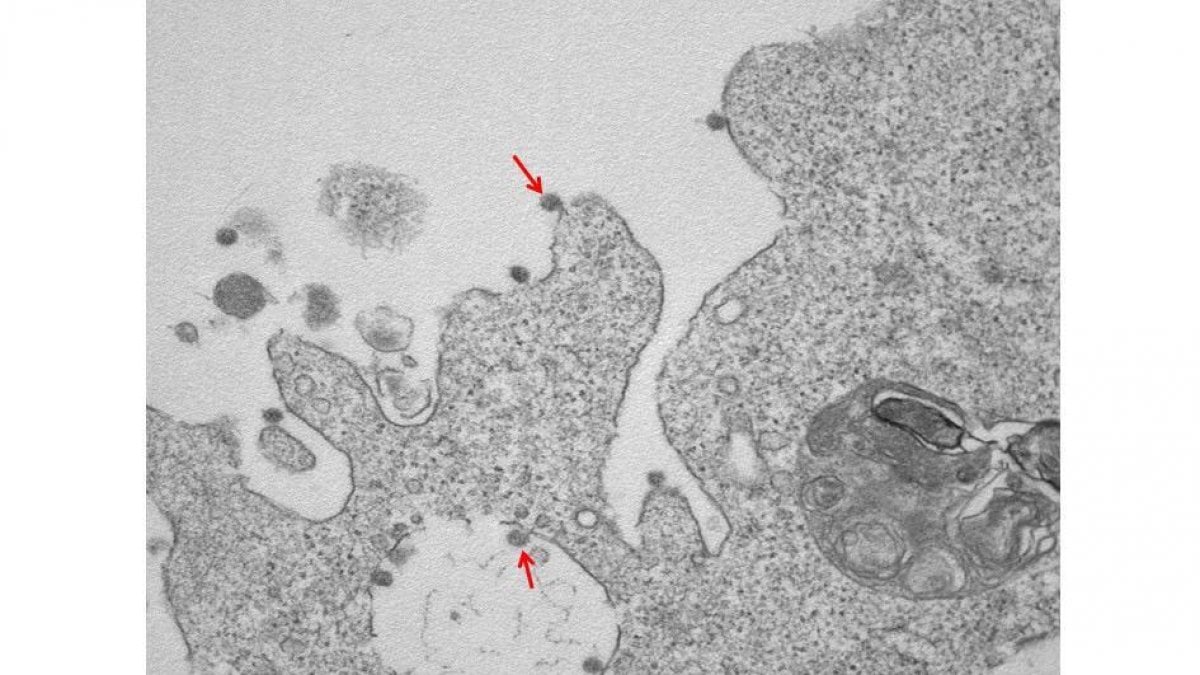

Η ομάδα ερευνητών του εργαστηρίου, σε συνεργασία με το τμήμα ανατομικής παθολογίας του νοσοκομείου, κατάφερε να απομονώσει τον ιό SARS-CoV-2 και να τον «φωτογραφίσει» μέσω ηλεκτρονικού μικροσκοπίου. Οι εικόνες που δημοσιεύτηκαν, δείχνουν τα ιικά σωματίδια που προσκολλώνται στις κυτταρικές μεμβράνες, μέσω της «κορώνας» των γλυκοπρωτεϊνών που διαθέτουν.

Συγκεκριμένα, η πρώτη φωτογραφία, που έχει μεγέθυνση 30000Χ «παρουσιάζει τα ιικά σωματίδια του Sars-CoV-2 να είναι προσαρτημένα στις επιφανειακές μεμβράνες και στο εσωτερικό κυττάρου».